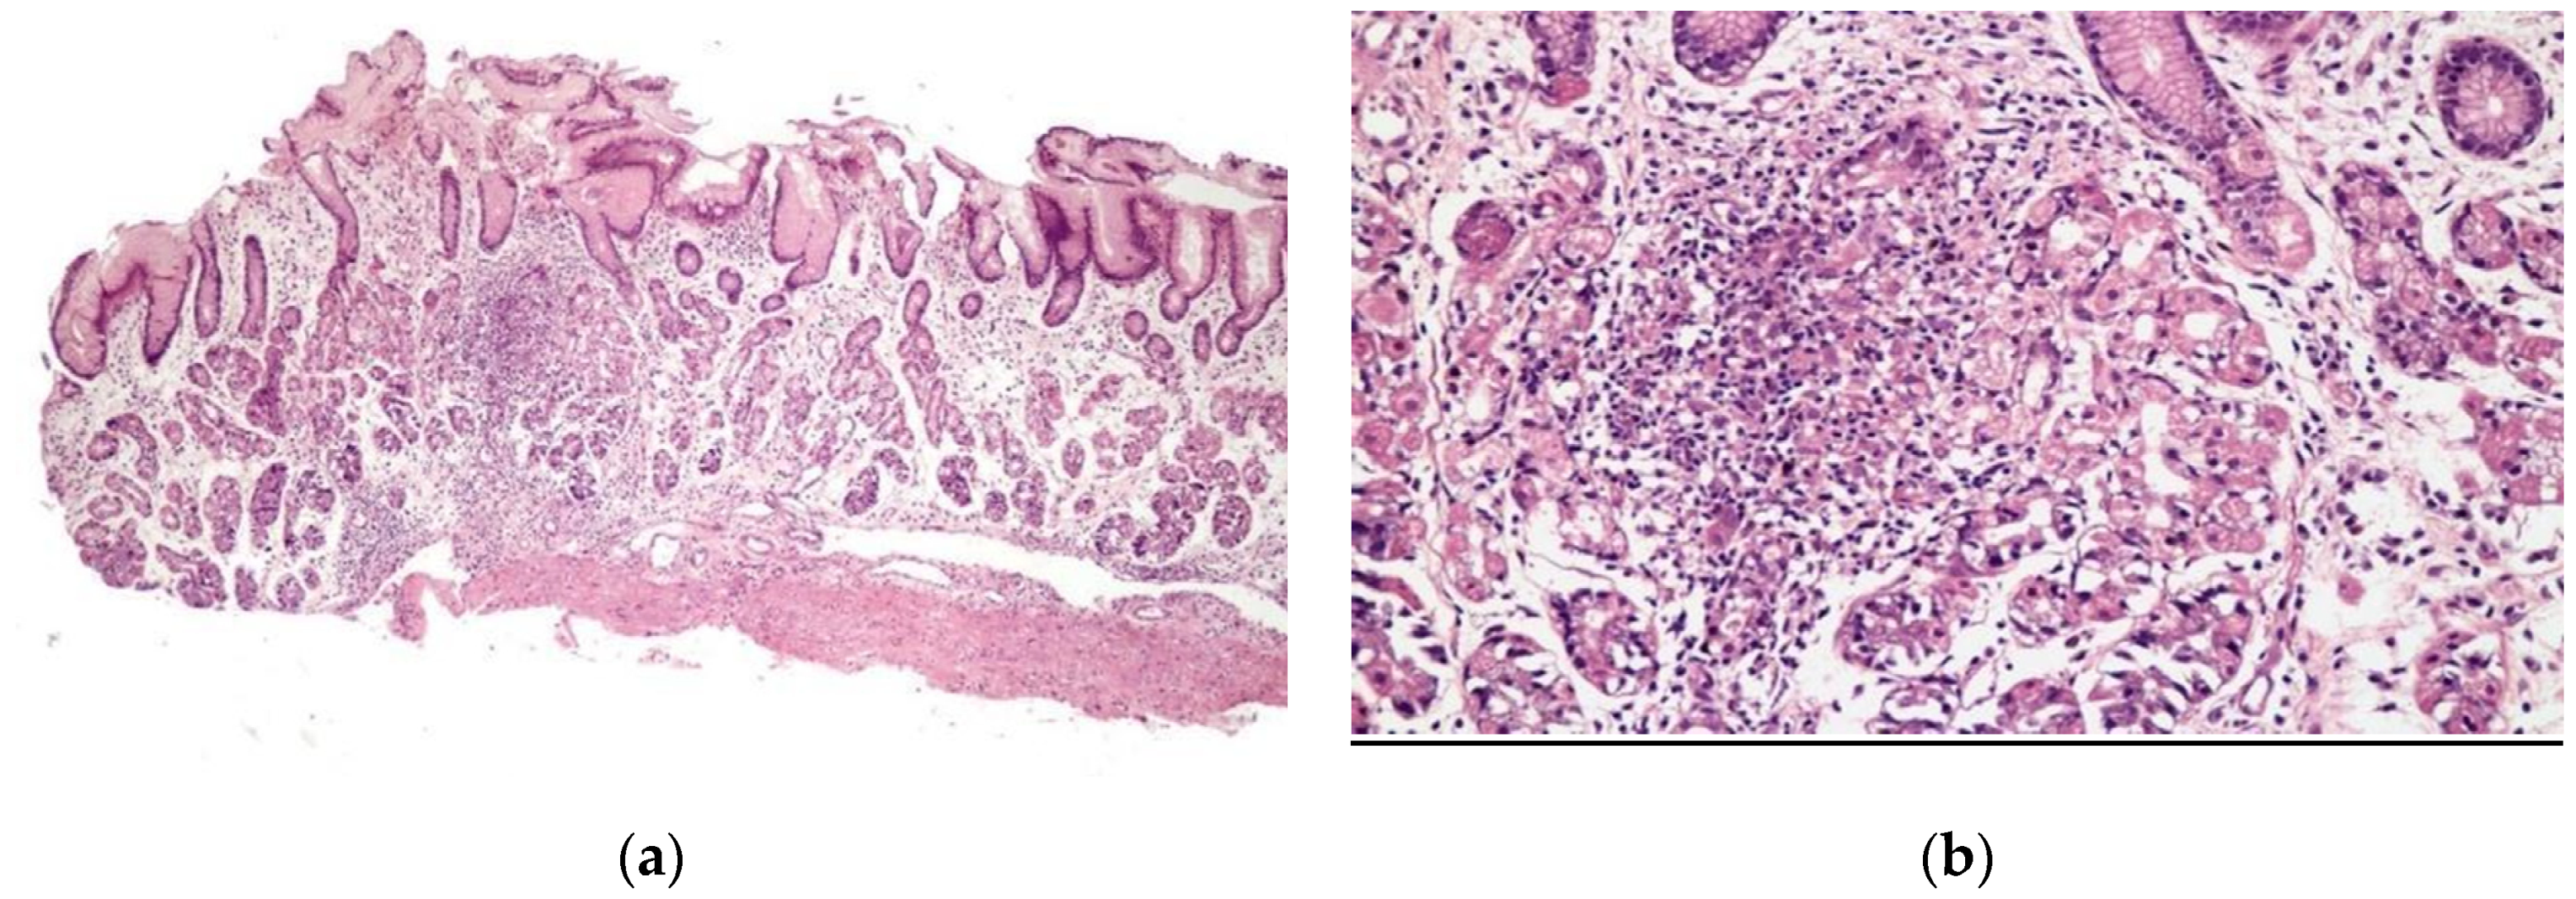

3.3. Histopathological Findings

3.4. Comparison between H. Pylori-Positive and H.-Pylori-Negative Patients